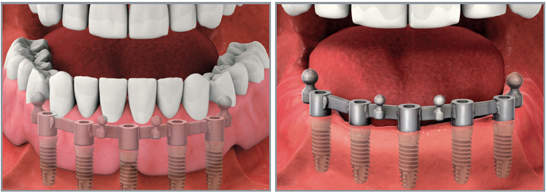

Сегодня распространены два типа крепления съемного протеза к имплантанту: балочный и кнопочный.

Крепление кнопочным замком

В данном случае в костную ткань челюсти вживляются имплантанты, имеющие округлую верхушку, для которых изготавливаются специальные протезы с внутренним углублением необходимой формы и микрозамком.

Попадая в такой замок, головка имплантата надежно фиксируется, делая невозможным смещение протеза в процессе жевания или во время разговора. При этом самостоятельно снять закрепленные таким способом протезы довольно просто — достаточно освоить одно специальное движение.

Такой тип фиксации рассчитан на использование 3-4 имплантантов для восстановления зубного ряда верхней челюсти, а также 2-3 имплантов при реконструкции зубов нижней челюсти. Тем не менее, следует учитывать, что использование минимально рекомендуемого количества имплантантов не всегда целесообразно и может привести к балансированию протеза в отдаленных отделах зубных рядов.

Протезирование на имплантах балочными конструкциями

Подобно предыдущему способу, первоначально в кость челюсти внедряют три и более имплантантов, но при этом между ними дополнительно устанавливается балка из металла, а в основании съемного протеза создается углубление соответствующей формы. Благодаря этому протез надежно фиксируется в ротовой полости и не сдвинется при активном движении челюстей.

В целом, такая система отличается более равномерным распределением нагрузки и очень проста в уходе.